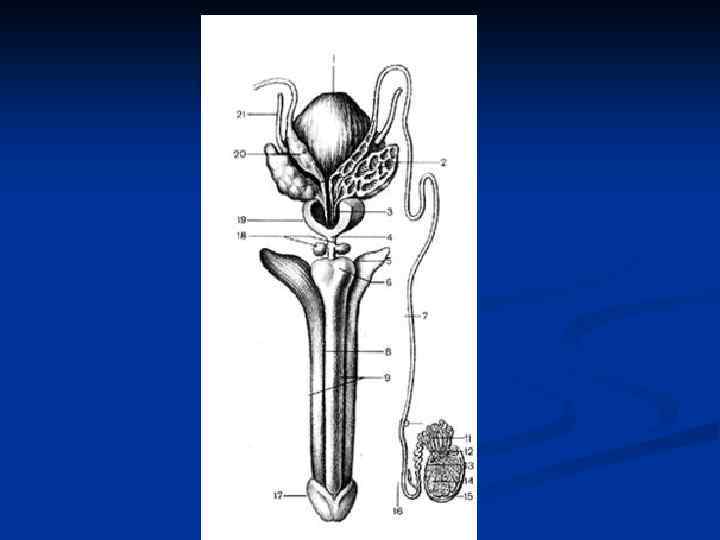

Мужские половые органы, organa genitalia masculina Наружные: 1. Мошонка, scrotum 2. Половой член Внутренние: 1. Яички с придатками 2. Семявыносящие и семявыбрасывающие протоки 3. Семенные пузырьки 4. Предстательная железа 5. Бульбоуретральная железа

Мужские половые органы, organa genitalia masculina Наружные: 1. Мошонка, scrotum 2. Половой член Внутренние: 1. Яички с придатками 2. Семявыносящие и семявыбрасывающие протоки 3. Семенные пузырьки 4. Предстательная железа 5. Бульбоуретральная железа

Путь выведения спермы: 1. Извитые семенные канальцы (700 -900) 2. Прямые семенные канальцы (250 -300) 3. Сеть яичка 4. Выносящие канальцы яичка (12 -15) 5. Проток придатка яичка 6. Семявыносящий проток (4 части – яичковая, канатиковая, паховая и тазовая) 7. Ампула семявыносящего протока + выделительный проток семенного пузырька 8. Семявыбрасывающий проток 9. Мужская уретра

Путь выведения спермы: 1. Извитые семенные канальцы (700 -900) 2. Прямые семенные канальцы (250 -300) 3. Сеть яичка 4. Выносящие канальцы яичка (12 -15) 5. Проток придатка яичка 6. Семявыносящий проток (4 части – яичковая, канатиковая, паховая и тазовая) 7. Ампула семявыносящего протока + выделительный проток семенного пузырька 8. Семявыбрасывающий проток 9. Мужская уретра

1. 2. 3. 4. 5. 6. 7. 8. 9. Путь выведения спермы: Извитые семенные канальцы (700 -900) Прямые семенные канальцы (250 -300) Сеть яичка Выносящие канальцы яичка (12 -15) Проток придатка яичка Семявыносящий проток (4 части – яичковая, канатиковая, паховая и тазовая) Ампула семявыносящего протока + выделительный проток семенного пузырька Семявыбрасывающий проток Мужская уретра

1. 2. 3. 4. 5. 6. 7. 8. 9. Путь выведения спермы: Извитые семенные канальцы (700 -900) Прямые семенные канальцы (250 -300) Сеть яичка Выносящие канальцы яичка (12 -15) Проток придатка яичка Семявыносящий проток (4 части – яичковая, канатиковая, паховая и тазовая) Ампула семявыносящего протока + выделительный проток семенного пузырька Семявыбрасывающий проток Мужская уретра